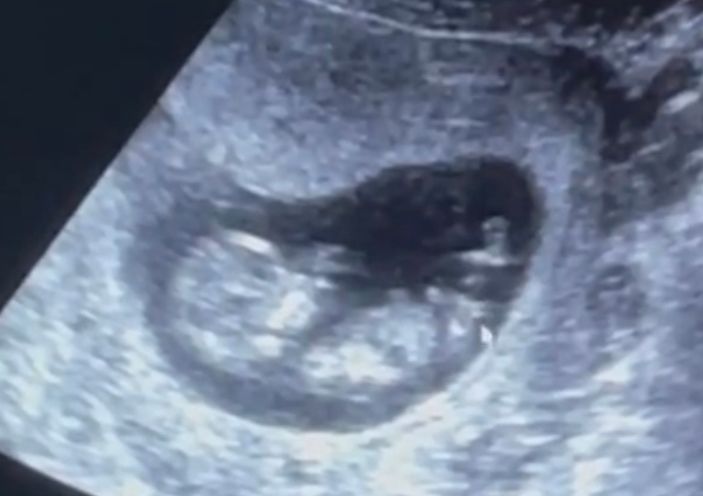

Была на узи в 12.5 Дважды, один врач говорит девочка 90%, второй что вроде на мальчика похоже, но не точно. Кто понимает, что скажите?На фото мышкой девочку показывает🤷🏻♀️

Мы точно по этому фото не определим,специалисты по сотню раз сидят на узи экранах,наверняка только они могу определять.Так что я бы врача слушала а не нас))Я тут даже разобраться не могу где у него(ее)тут попа